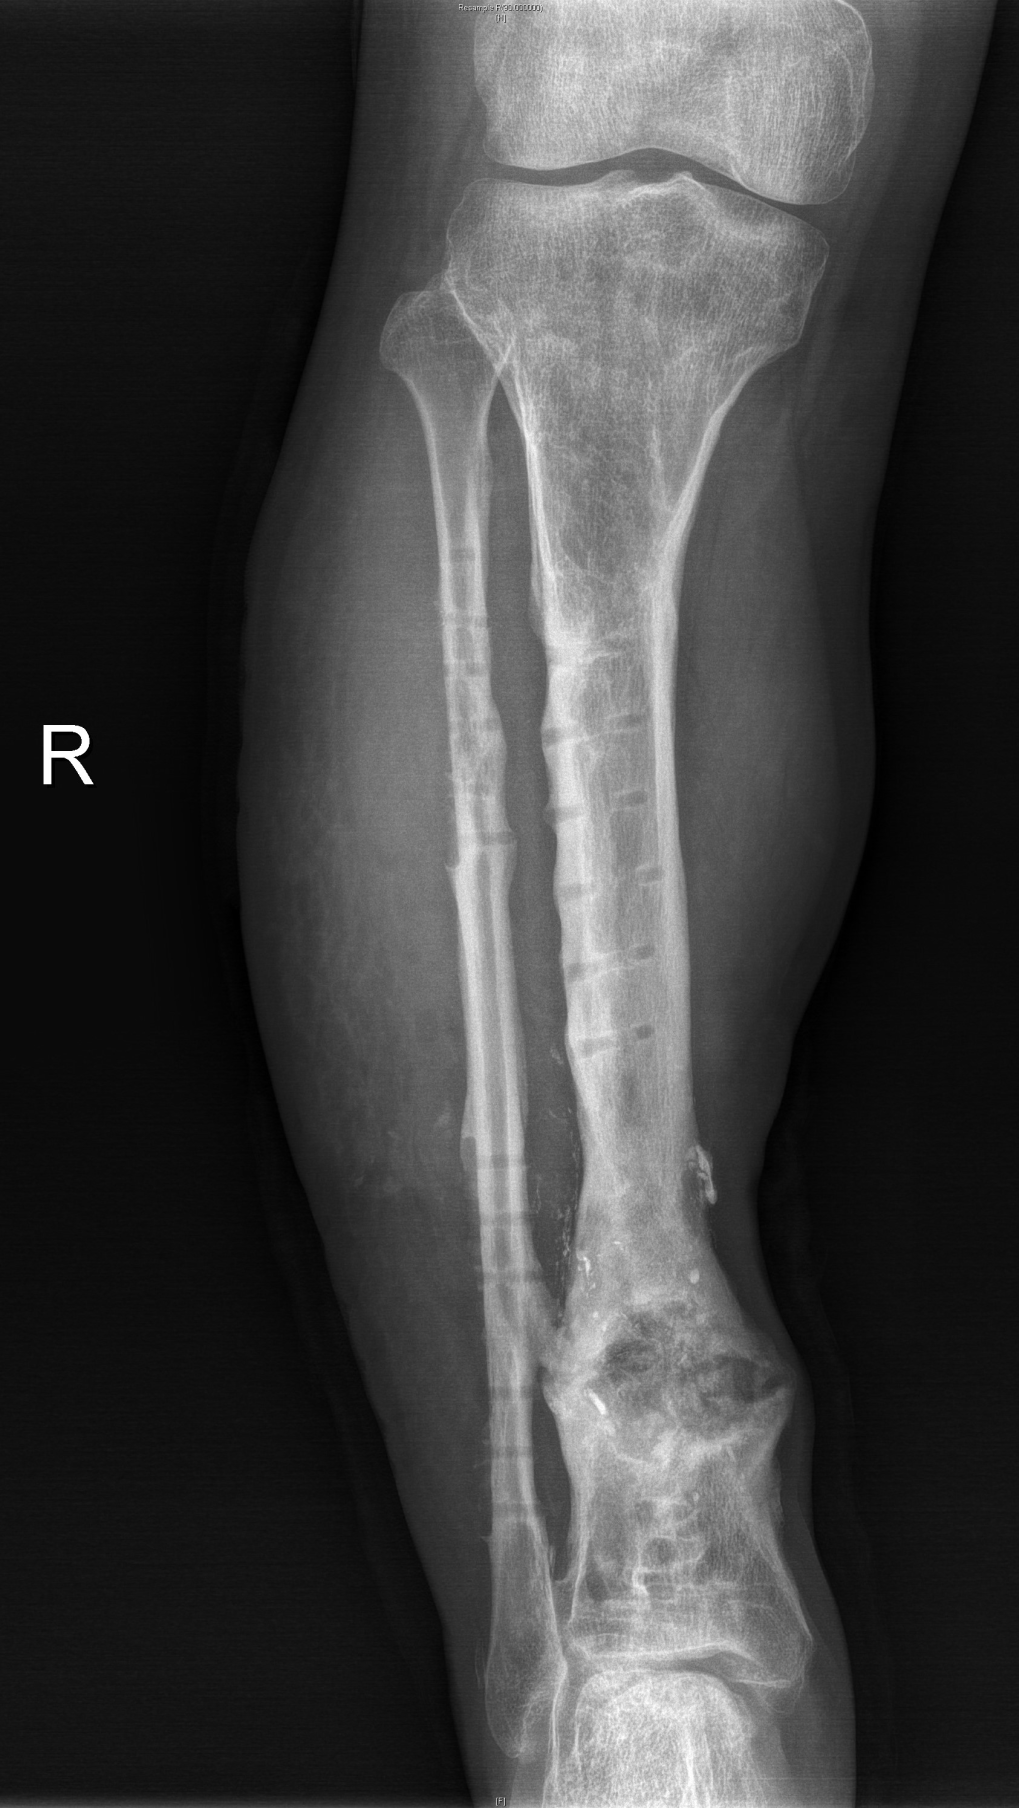

▲外院清创固定术后图

徐杨主任医师、许春财副主任医师在全面评估后,考虑小罗右小腿虽然皮肤肌肉溃烂、缺损,胫骨大段缺损,合并严重多重耐药菌(MRSA)感染,血管神经也均有较严重损伤,但残留胫后血管尚能维持远端血供,这将是小罗保住右腿的一线希望!

经过反复评估及推敲,徐杨主任医师决定分三步进行:首先分次清创,在保住残留血供及神经同时,彻底清创;利用长管状骨节段性缺损诱导膜再生技术(masquelet技术)修复骨缺损,最后通过肌腱转位替代、踝关节松解,恢复功能。这其中每一步都不容有失,困难重重,极具挑战。在医患通力配合下,多次按既定方案为小罗成功施行手术,小罗保住了右腿,经过近一年的正常行走生活,近日返院进行最后的钢板拆除手术。